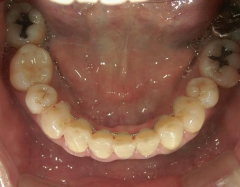

矯正歯科 治療後矯正歯科 プチワイヤー矯正 治療後矯正歯科(プチワイヤー矯正)治療後

矯正歯科 治療後

矯正_灰色.pngno.12_5333_治療後_下.jpg矯正_灰色.png